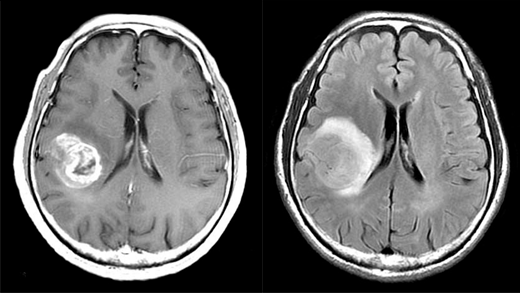

脳腫瘍とは、脳の表面や組織にできる腫瘍の総称です。脳腫瘍は脳の細胞や神経・脳を包む膜から発生する原発性脳腫瘍と、肺がんや乳がんなどが脳に転移する転移性脳腫瘍と大きく2つに分けられます。

腫瘍ができていても症状が出ないこともありますが、進行すると、起床時の頭痛、嘔吐などが起こることがあります。また、腫瘍ができる場所によっては、神経脱落症状(片麻痺や言語障害など)、聴力障害、視野障害、またはてんかん発作などの症状がみられることもあります。